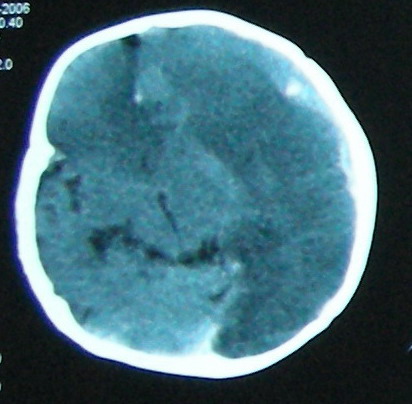

左侧大脑半球和右侧额叶大片低密度影,脑沟及外侧裂池消失,左侧脑室闭合,考虑脑梗塞伴有水肿。

考虑:1、左额颞顶慢性硬膜下血肿(可能为产伤所致);

2、蛛网膜下腔出血;

3、左侧大脑半球及右额叶脑肿胀、梗塞(缺血性脑梗塞为脑疝所致)。

左额颞顶慢性硬膜下血肿(可能为产伤所致);蛛网膜下腔出血,已明确,至于左侧大脑半球大片低密度影并脑组织肿胀,考虑:梗塞导致缺血缺氧性改变.至于梗塞原因随诊观察吧!

左侧大脑半球和右侧额叶大片低密度影,脑沟及外侧裂池消失,左侧脑室闭塞,左侧蛛网膜下腔片絮状高密度影,结合病儿高热、脑膜刺激征(+),考虑:炎脑,脑水肿,左侧蛛网膜下腔出血。至于出血原因,应该为高热所致维生素c需要量增加,而补给不足所致维生素c缺乏,抑或是使用抗惊厥药影响维生素k代谢,使凝血发生障碍而出血。当然,一切都是猜测,需要临床进一步检查验证。